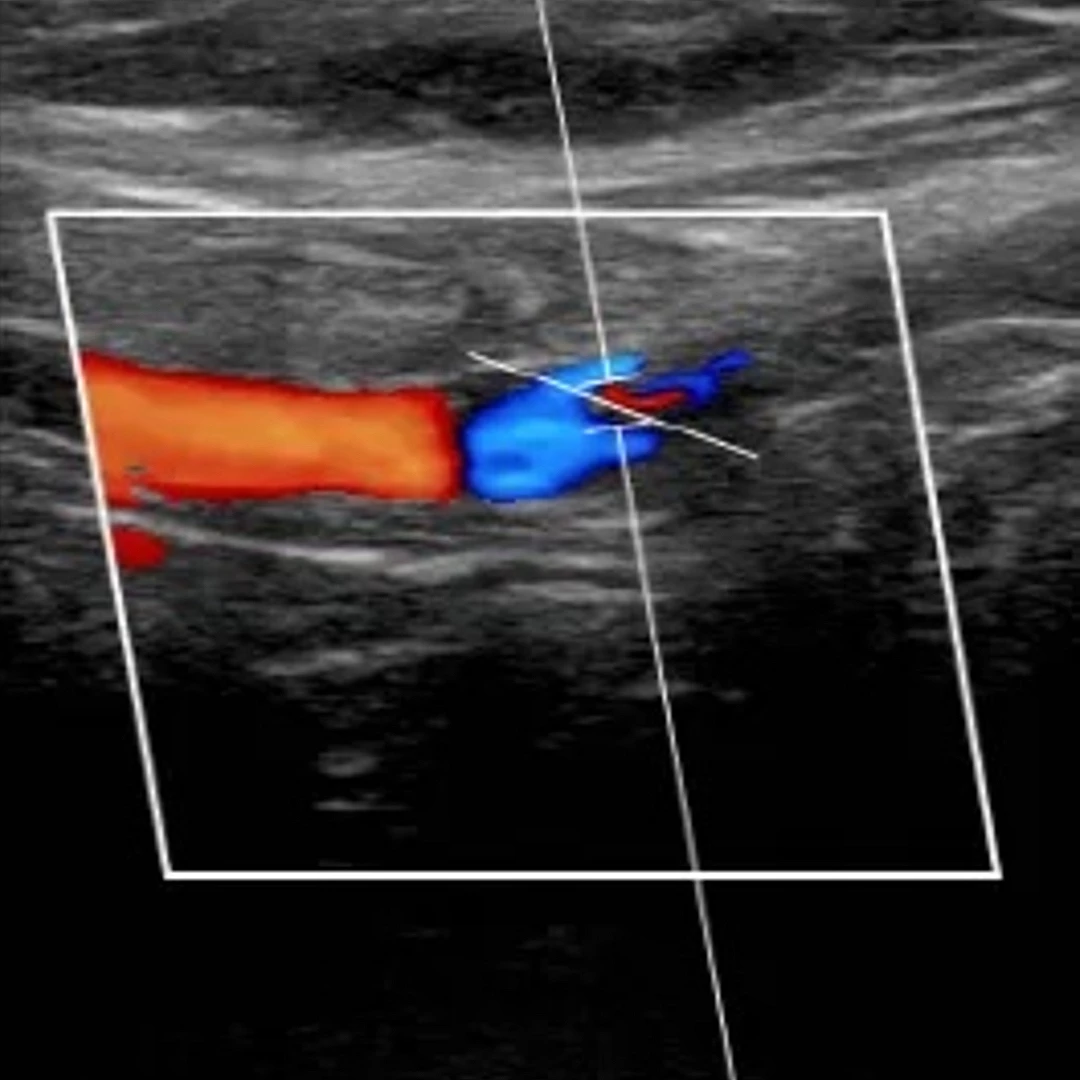

Aortic & Peripheral MR Angiography

Aortic and Peripheral Vascular Ultrasound visualizes blood flow in the aorta and limb arteries to detect aneurysms, blockages, or vascular disease. It’s a safe, non-invasive scan that provides real-time assessment of circulation and vessel health for accurate diagnosis and treatment planning.